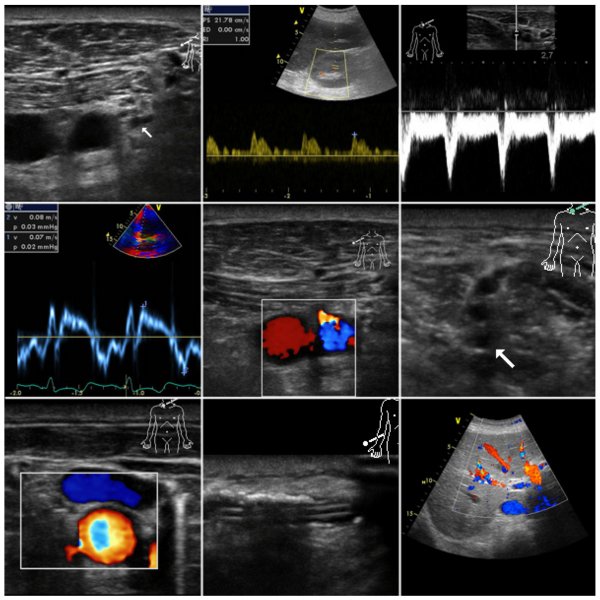

Der Einsatz von Ultraschallgeräten zur Diagnostik sowie Intervention ist mittlerweile aus dem anästhesiologischen und intensivmedizinischen Alltag nicht mehr wegzudenken. So ist es verständlich, dass die Ausbildung in der Ultraschalldiagnostik und der ultraschall-gesteuerten Punktionen für Anästhesistinnen und Anästhesisten eine wachsende Bedeutung einnimmt. Dies spiegelt sich auch in den Fachgesellschaften wieder, die der Ausbildung einen immer höheren Stellenwert beimessen.

Aus dieser steigenden Bedeutung der Sonografie für Anästhesisten und Intensivmediziner erwächst die Verpflichtung, didaktische Konzepte zu entwickeln, um eine erfolgreiche Vermittlung des komplexen Wissens zu gewährleisten. Der inhaltliche Rahmen ist durch den Anforderungskatalog der DEGUM (Deutsche Gesellschaft für Ultraschallmedizin) sowie der DGAI (Deutsche Gesellschaft für Anästhesiologie und Intensivmedizin) vorgegeben. Das von der münsterschen Klinik für Anästhesiologie entwickelte Ausbildungskonzept erfreut sich seit 3 Jahren einer großen Beliebtheit. Dabei wird auf eine didaktische Ausrichtung des Kurses mit einem starken Praxisbezug und einem hohen Anteil von praktischen Übungen in Kleingruppen großer Wert gelegt.